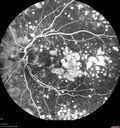

79 year old vision is in for a checkup with no visual complaints in the left eye. This is her better eye. VA 20/200 OD, 20/50 OS. 3 years ago she had a CRVO in the left eye. She is also diabetic for 20 years, has carotid insufficiency and anemia. Left eye shows CME. This was not treated and the vision improved to 20/40 over the next year although mild edema persisted.